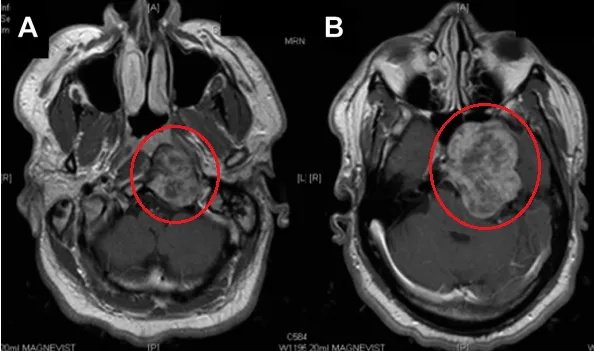

MR检查:颞下和斜坡区域较大肿瘤(脊索瘤可能),存在广泛的岩骨和斜坡骨质侵蚀,肿瘤并向海绵窦侵袭(图A-B)。

图A和B:增强磁共振T1加权像显示颞下窝较大占位,肿瘤延伸至舌下神经管(HC)水平的咽后间隙。肿瘤向前侵犯蝶窦,并向后颅窝和中颅窝浸润,无硬膜内浸润。